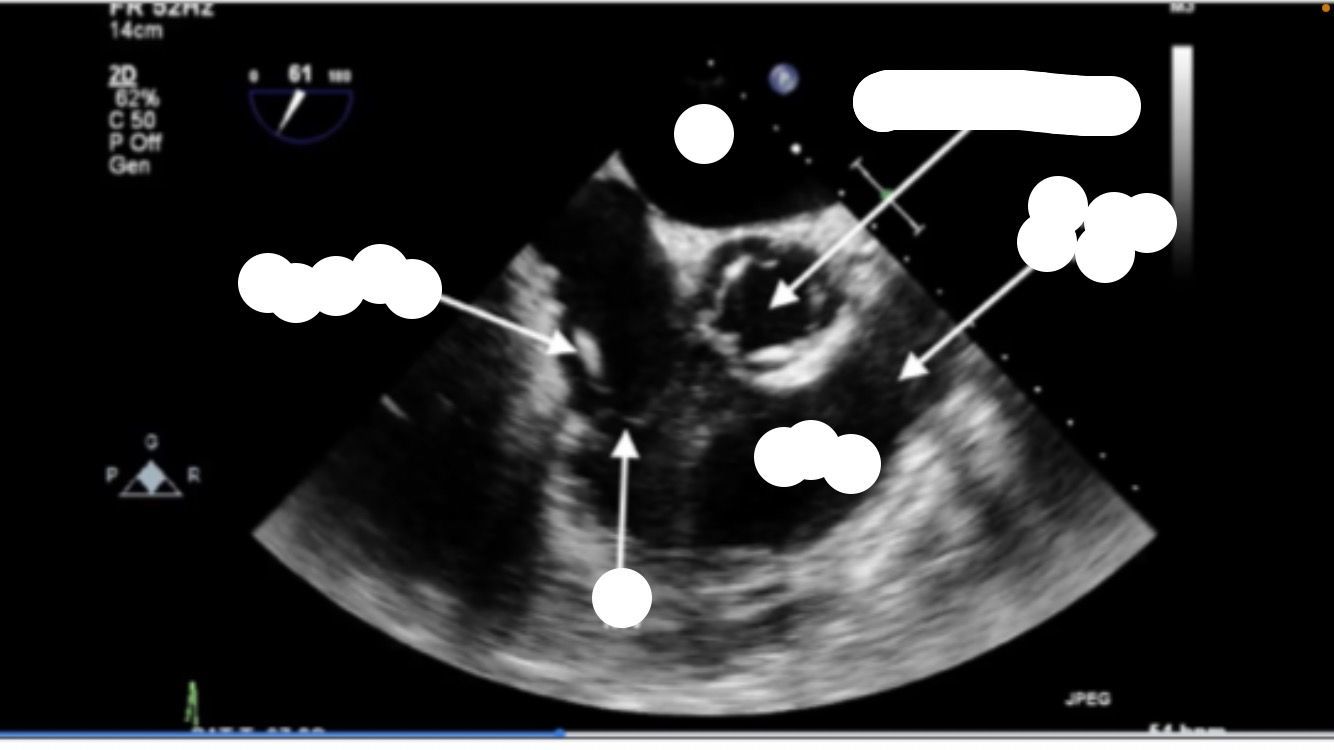

Mid esophageal RV inflow and outflow

TRICUSPID NOT MITRAL VALVE